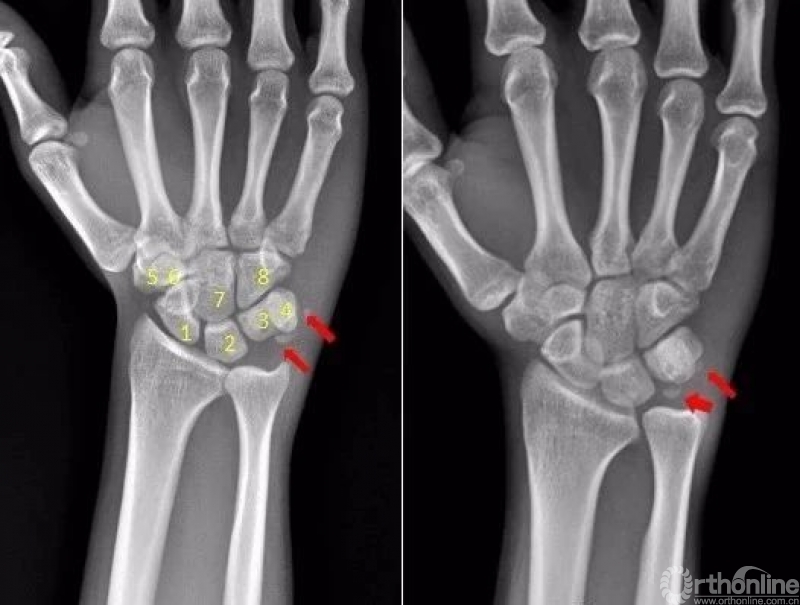

腕关节

1.舟骨 2.月骨 3.三角骨 4.豌豆骨 5.大多角骨 6.小多角骨 7.头状骨 8.钩骨

右腕关节近三角骨、豆状骨内侧见多个游离骨碎片影,小碎骨片分离移位。考虑为,右腕关节三角骨,豌豆骨粉碎性骨折

右侧桡骨远端可见不规则透亮骨折线,并累及关节面。右侧桡骨远端骨折

尺骨茎突见游离骨碎片影。左侧尺骨茎突骨折